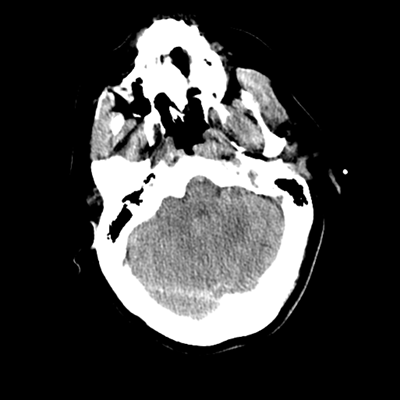

The patient goes down to CT. The following images are obtained. The subdural fluid collection is stable, as is the ventricular caliber.

Starting with the non-contrast head CT, we can appreciate that there's actually not much residual subarachnoid blood at all; it's essentially all resorbed already (and cleared through the EVD). The ventricular caliber is stable. With the CTA head (for convenience's sake, the MIPs were shown), it's subtle, but we can see that the PCAs on each side are not as smooth and regular. The right MCA, starting at the bifurcation, also becomes narrower. This is [radiographic] vasospasm. Now, looking at the CT perfusion-- specifically, the Tmax (MTT) map that were selected-- there's clearly some abnormality within the bilateral cerebellar hemispheres and occipital lobes. Not a lot, but it's there. Delving further into this map, we can appreciate that the areas of abnormality are mainly green, signifying that these areas have Tmax > 6 seconds. This is the threshold that is specific, not sensitive, for vasospasm.

Putting this all together, we have thus identified radiographic vasospasm with the vessel imaging, with perfusion abnormalities that are concordant with it. Does the area of vasospasm and hypoperfusion correlate with the patient's clinical exam?

Yes! It does. The patient had a decline in level of consciousness with diffuse loss of motor function. This does correlate to the basilar territory. (Alternatively, bilateral MCA vasospasm could also be responsible, reminding us that a decline in consciousness could technically be focal/multifocal.) Thus, we can say that this patient does have clinical vasospasm. Whether this will develop into irreversible DCI remains to be seen; at least, the non-contrast head CT and the other portions of the CT perfusion (not shown) currently don't [yet] suggest infarction.